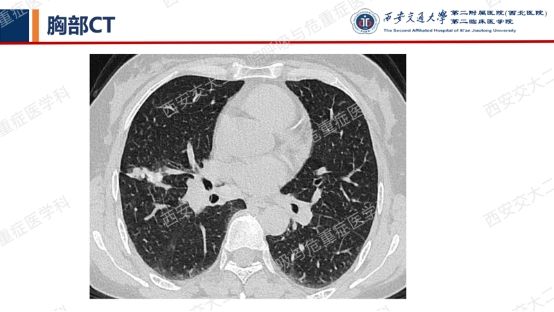

影像方寸藏玄机,同影异病辨真章。第一期我们就弥漫性囊性肺疾病的诊断做了粗略分析,除BHD、LAM等疾病外,还有其他一些疾病也需要我们仔细鉴别。在上期的解析中,我们留下了2例影像资料大家温故知新,相信通过系列的学习,大家很快会得出精准的答案。今天就让我们继续一起抽丝剥茧,揭秘医学真相,继续解锁临床那些有意思的病例谜题吧!

结合以上病史及胸部CT,您的初步考虑?还需要哪些检查?